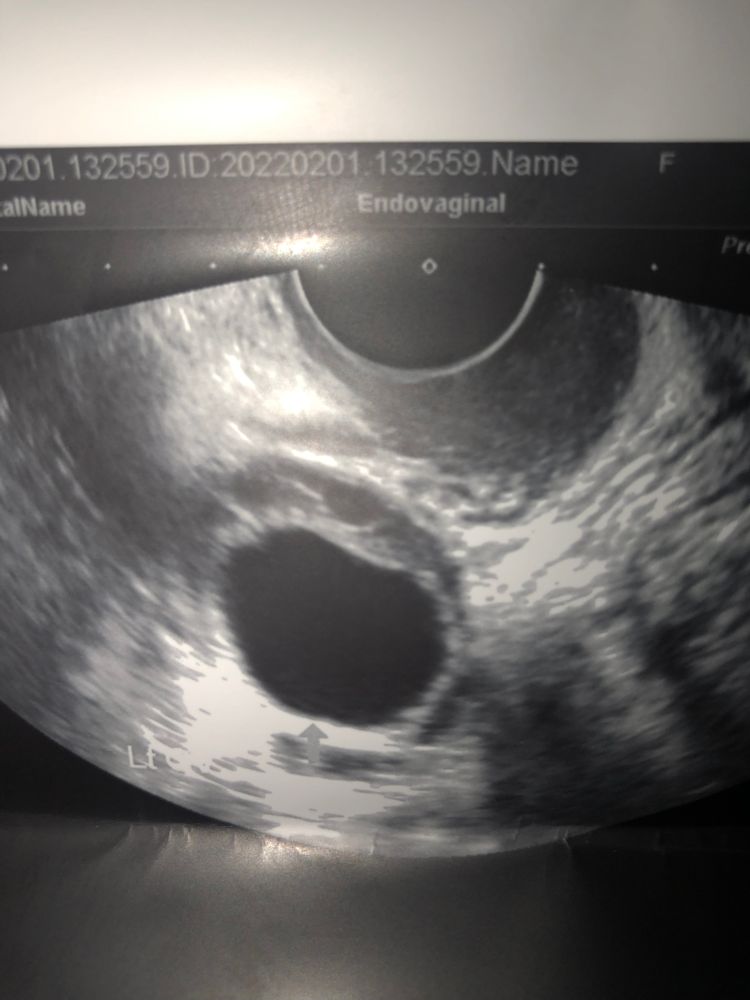

Арина С, почему?а на первом узи это что было интересно? Изображение

bravo gun, на этом фото могу предположить фолликул, большой, но у меня и до 25 мм дорастали и затем была овуляция.

Арина С, во вторник была такая «фолликулярная киста» как сказал узист,а в среду вообще ничего не было там,получается был доминантный фолликул скорее всего